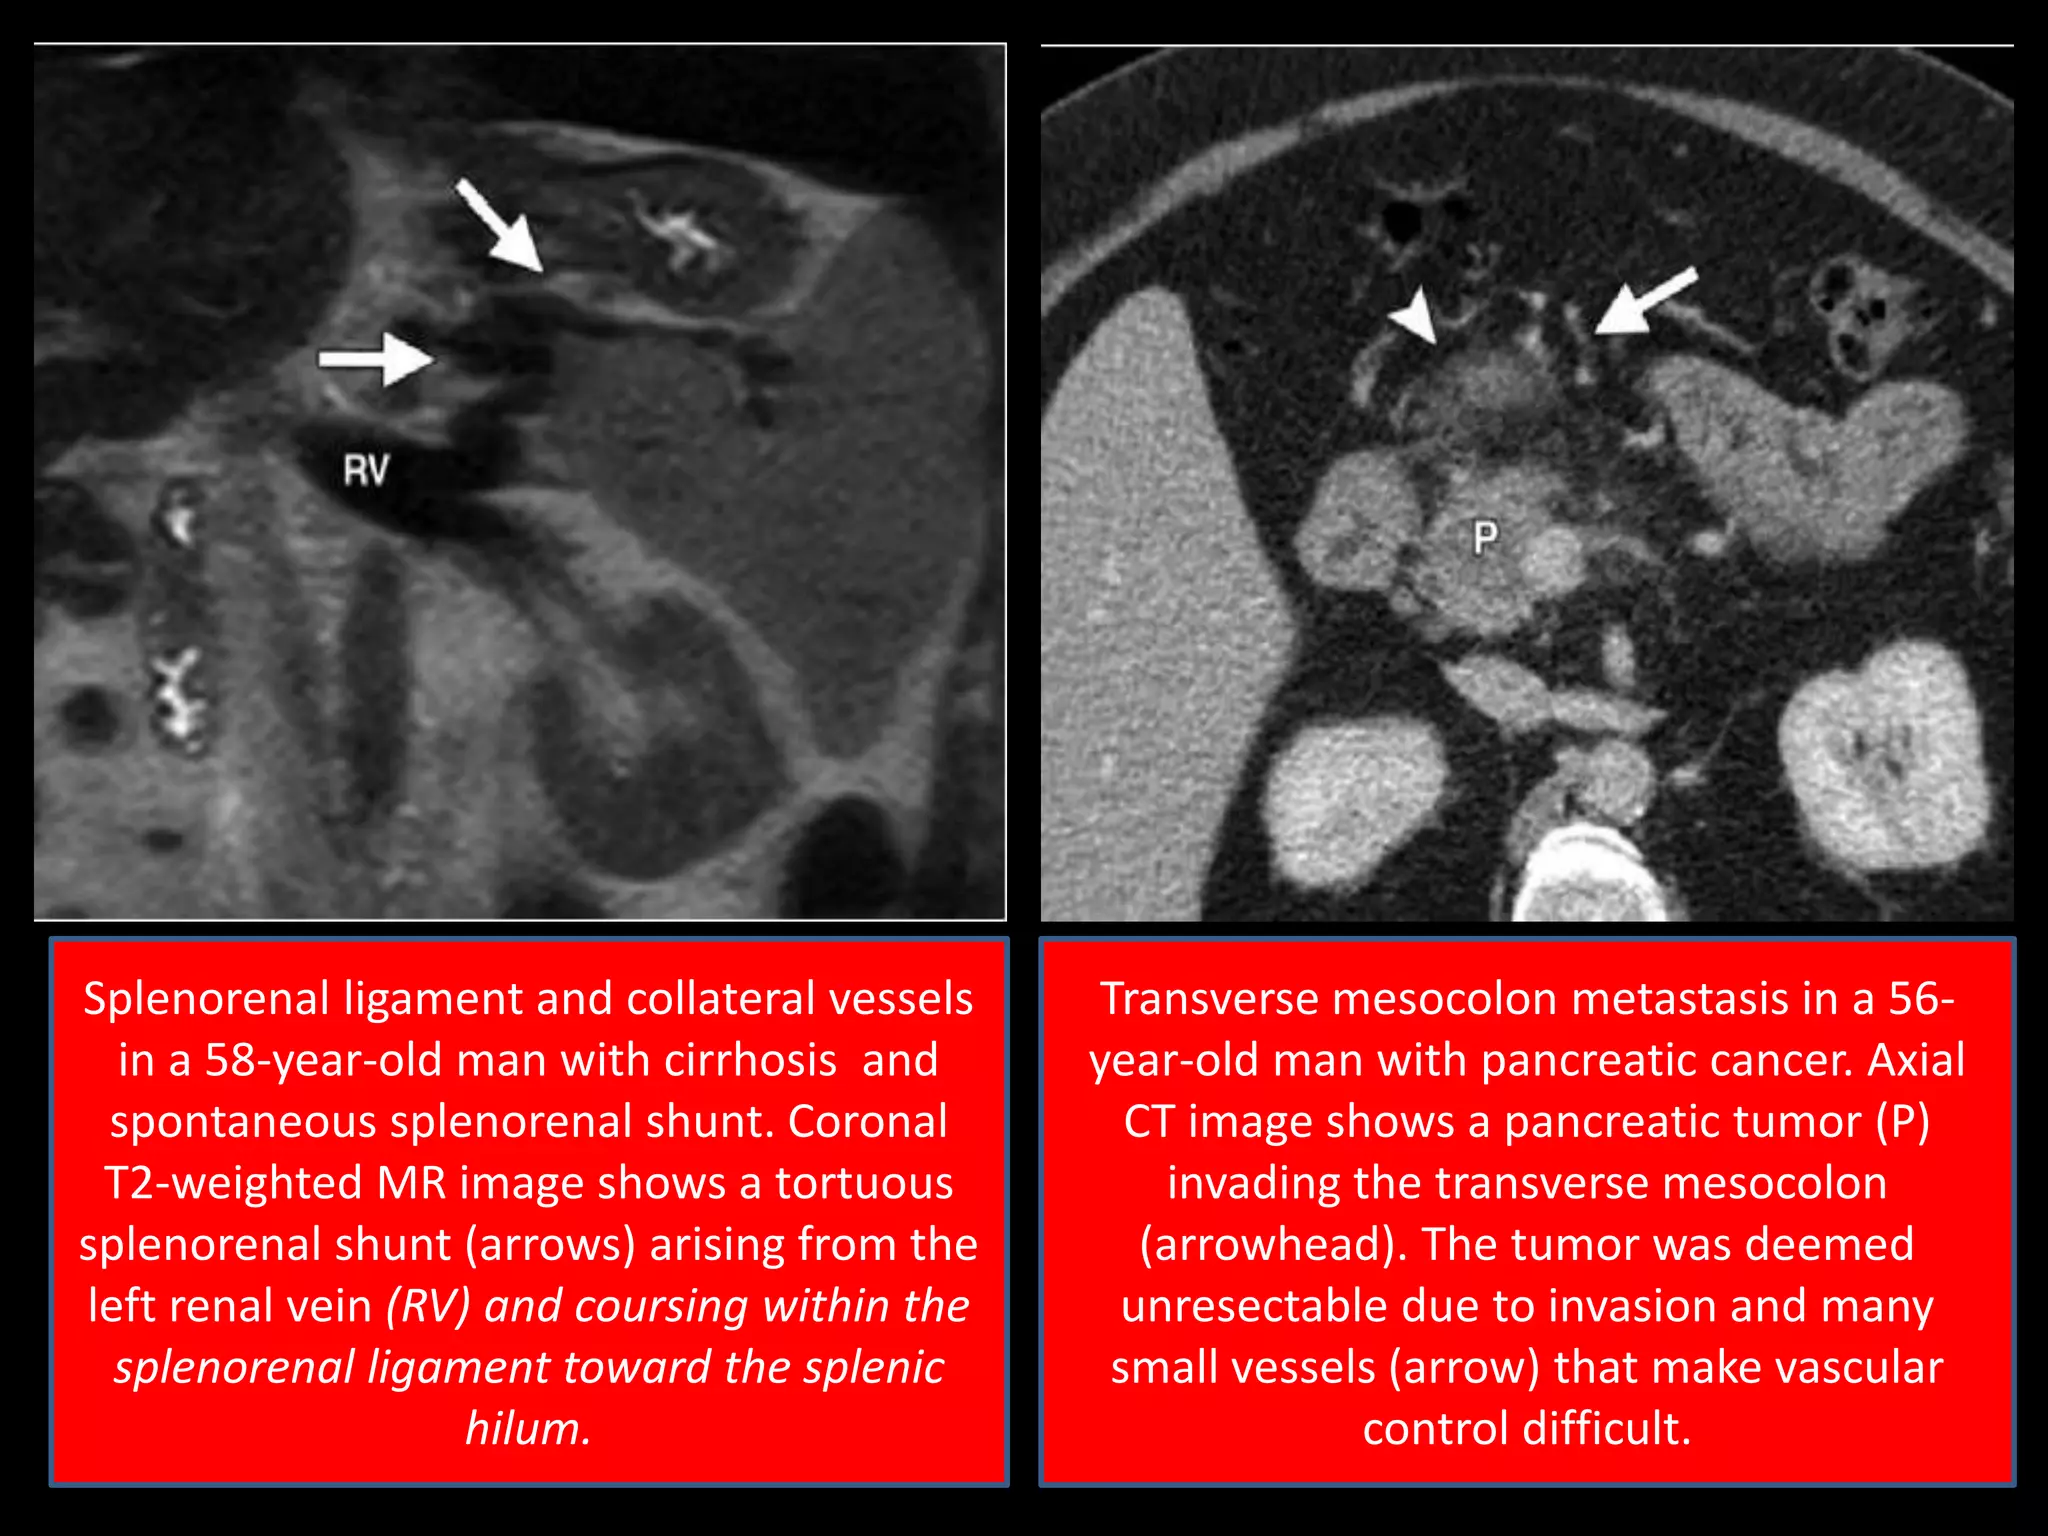

Splenorenal ligament and collateral vessels

in a 58-year-old man with cirrhosis and

spontaneous splenorenal shunt. Coronal

T2-weighted MR image shows a tortuous

splenorenal shunt (arrows) arising from the

left renal vein (RV) and coursing within the

splenorenal ligament toward the splenic

hilum.

Transverse mesocolon metastasis in a 56-

year-old man with pancreatic cancer. Axial

CT image shows a pancreatic tumor (P)

invading the transverse mesocolon

(arrowhead). The tumor was deemed

unresectable due to invasion and many

small vessels (arrow) that make vascular

control difficult.